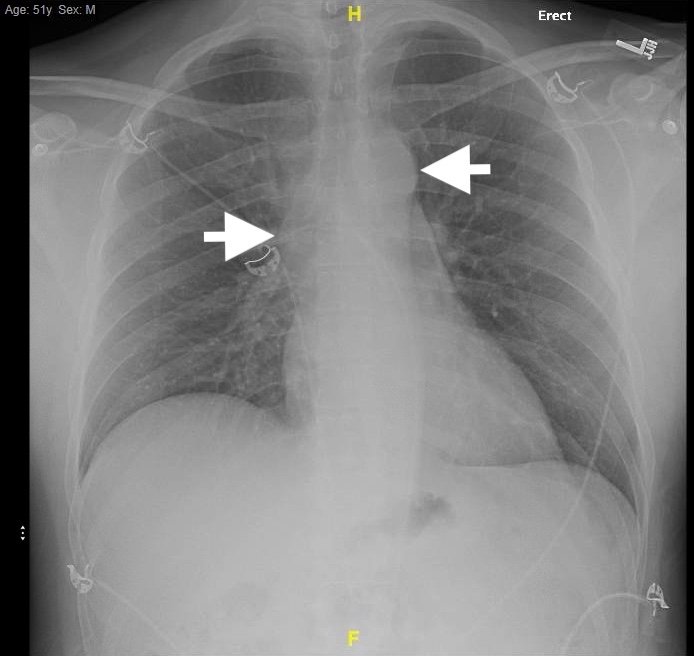

We present a case of a 51-year-old previously healthy man who presented to the ED complaining of chest pain that had resolved prior to arrival, and a mild headache. His vital signs were notable for hypotension, but physical exam was unremarkable. Chest x-ray revealed a borderline widened mediastinum. A standard ETTE was within normal limits, but additional SSNV demonstrated a dissection flap in the aortic arch. The patient was taken to the operating room for surgical repair 75 minutes after the ED ultrasound was performed; the operation was successful, and the patient was discharged to home post-operatively with good outcome.